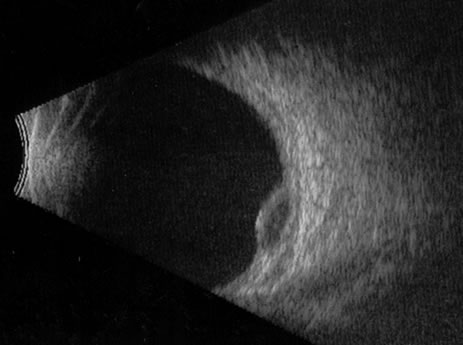

Necrotic melanomas account for approximately 5% of uveal melanomas; in the majority of cases, there is intraocular inflammation accompanying the cataract.7–9Figures 1 and 2 demonstrate a typical case. The patient had a long history of unilateral decreased vision. The eye had become painful 1 month before admission, and he was referred for evaluation of uveitis. Clinically, there was a dense, unilateral cataract with significant intraocular inflammation, which was manifested as a ciliary flush with 2+ cells and flare. Media opacity obscured all fundus detail. An immersion B-scan demonstrated a large intraocular tumor that was most consistent with a uveal melanoma. The eye was removed, and the diagnosis was confirmed histologically.10

Fig. 1. A unilateral media opacity in an adult, requiring that either a foreign body or an intraocular tumor be ruled out. The finding of a large episcleral (“sentinel”) vessel was consistent with either an intraocular tumor or an inflammation. An immersion B-scan helped determine the diagnosis (see Fig. 2).

Fig. 2. Immersion B-scan of the patient in Figure 1 demonstrates a uveal melanoma.